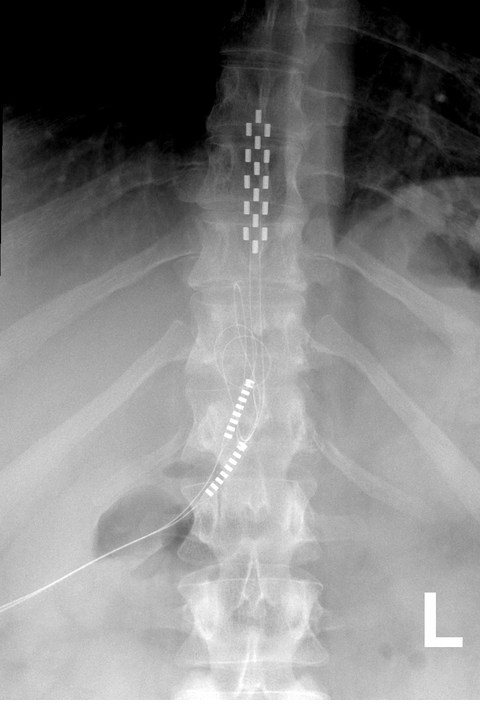

Neurocirurgia Funcional

Doença de Parkinson, Tremor Essencial, Distonia, Espasmo Hemifacial e mais...

Tratamento da Dor

De forma geral, existem duas categorias de dor: a dor aguda e dor crônica. Ambas podem se manifestar de forma leve, moderada ou severa e sua etiologia é variada : dor neuropática, nociceptiva, nociplástica, mista... A dor crônica é aquela que tem duração superior a três meses. Existem diversas abordagens possíveis.

Prezamos por um abordagem cuidadosa, combinada a técnicas modernas que proporcionam mais qualidade de vida ao paciente.